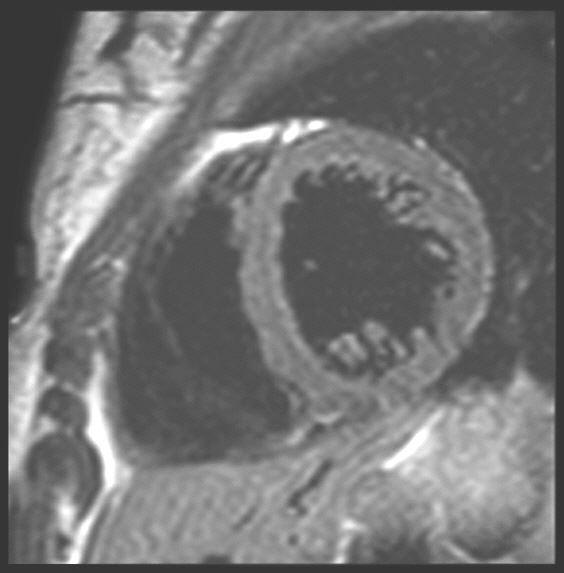

Die MRT des Herzens (Cardio-MRT) ist dabei eine besondere Herausforderung. Schon heute kann dieses Verfahren sehr gut Entzündungen und Durchblutungsstörungen sowie andere Schäden des Herzmuskels mit hoher Auflösung sichtbar machen. Bewegte Bilder der Herzaktionen lassen Schäden des Herzmuskels erkennen. Siehe auch Herz- und Blutgefäße.

MRT Herz

Während die Herzkranzgefäße noch nicht ausreichend zuverlässig beurteilt werden können, kann die MRT z.B. vor Bypassoperationen zwischen Infarktnarben des Herzmuskels und Zonen der Minderdurchblutung differenzieren.